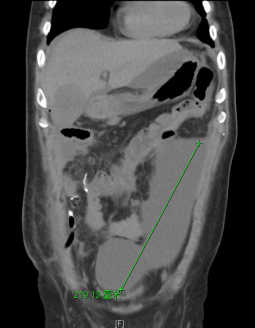

入院后完善相关辅助检查,经引流管造影评估后更换双套管引流右侧腹腔,腹部CT可见腹腔内大量积液,经CT定位后局麻切开引流。

患者经主动冲洗引流右侧腹腔和局麻引流左侧腹腔积液后各项感染指标明显改善。最终用生物蛋白胶将右侧瘘口进行封堵。